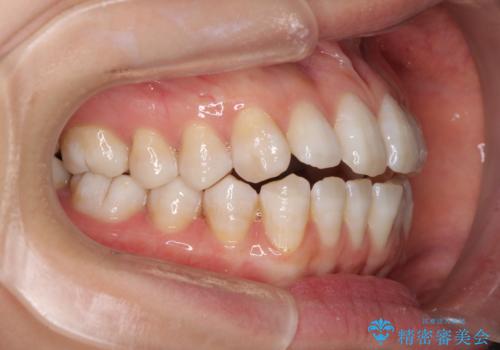

話しにくいオープンバイト インビザラインによる矯正治療

- 前歯の上下スペースによる話しにくさを気にして来院された患者様です。

インビザラインにより上下の前歯の隙間を閉じていくこととしました。

上下の奥歯を圧下させるようにすることで、前歯を接触させるように計画しました。

隙間に舌が入り込むことが話しにくさに繋がっていたため、舌の筋肉のトレーニングも並行して行い、話しにくさの改善と後戻りの抑制を図りました。